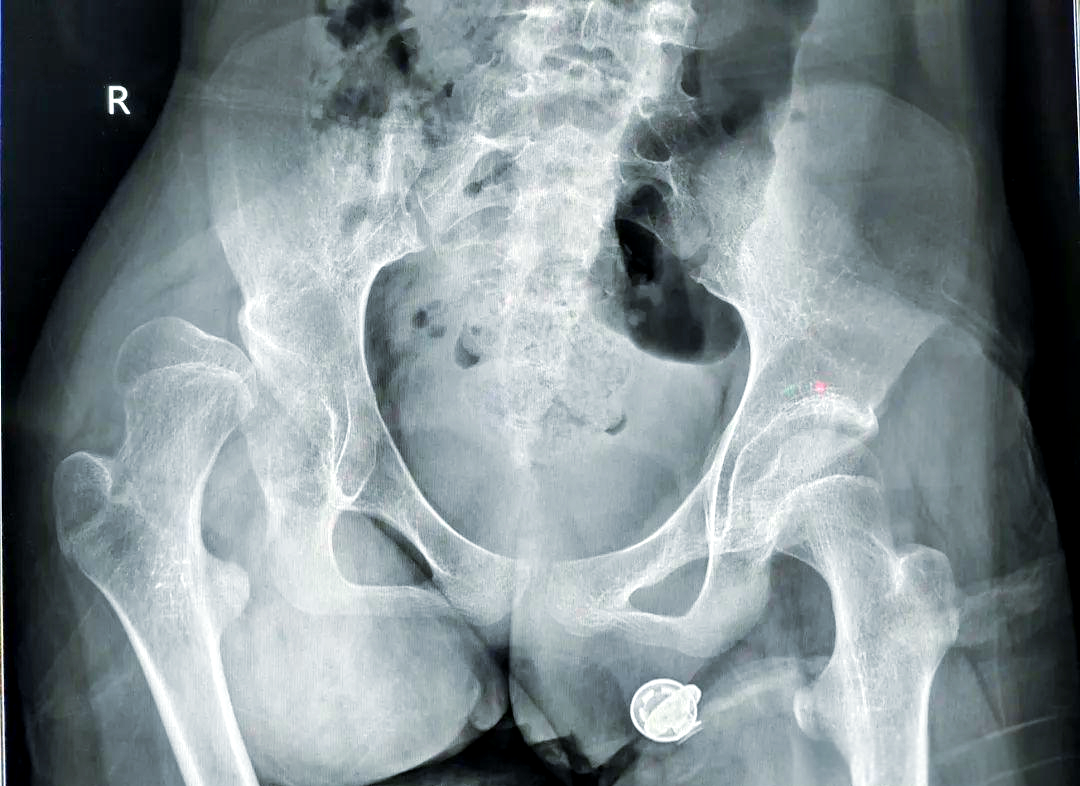

婴儿髋关节脱位的表现有哪些

小儿髋关节脱位的表现因年龄阶段不同而有所差异,具体如下新生儿及婴幼儿期出生至1岁左右主要表现为臀纹不对称,即两侧臀部皮肤褶皱的深度数量或位置不一致,这是早期最常见的体征之一同时,可能出现双下肢不等长,患侧下肢较健侧短...